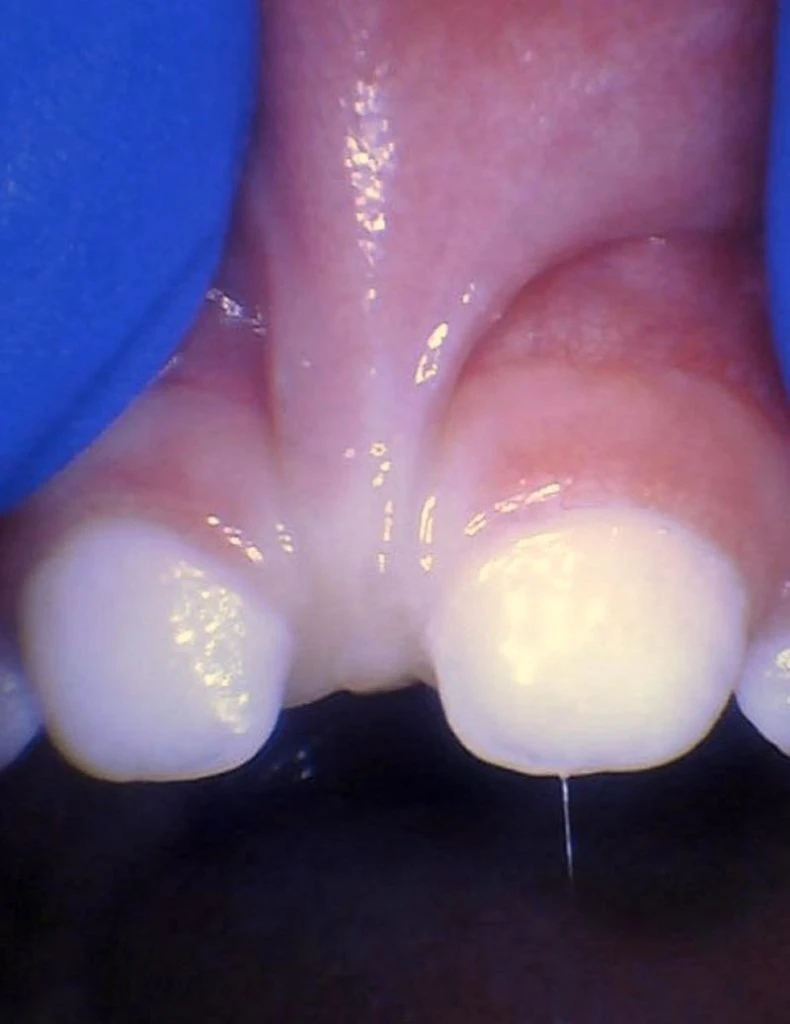

These images show the spectrum of lip restriction in an infant.

View lip restrictions

These images show the spectrum of lip restriction in a child.